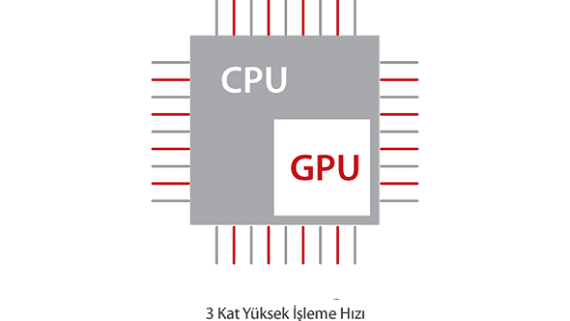

Mindrayâin yeni ??zĂŒmĂŒ, geli?en en yeni ultrason teknolojileri ile birlikte, mĂŒ?terilerin g?rĂŒ?lerini klinik gerekliliklerle tam anlam?yla birle?tiren bir ??zĂŒmdĂŒr. Taptaze bir ruhla, gelece?e odaklanarak ve s?n?rs?zl???n pe?inde ko?arak, artan ?l?eklenebilirlikte sĂŒrekli olarak geli?en bir ??zĂŒmdĂŒr.

MĂŒ?teri gereksinimlerine y?nelik g?rĂŒ?ler temelinde, X-Insight'l? DC-60 Exp, eXpress Clarity, eXceptional Intelligence ve eXceeding Experience ile gĂŒ?lendirilerek, hassas g?rĂŒntĂŒlemeyle yĂŒksek verimlilik sa?layacak ?ekilde tasarlanm??t?r.